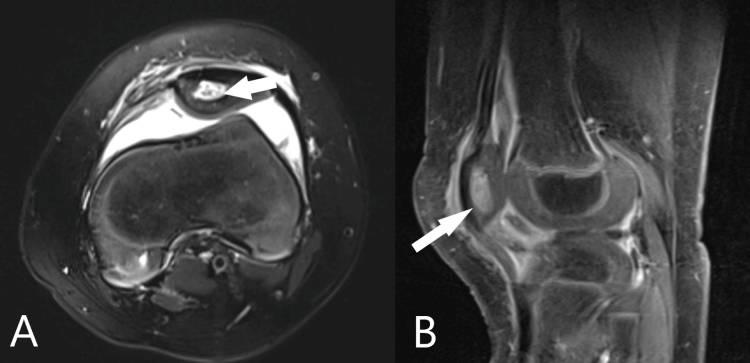

手术后几天,出现髌前肿胀、皮疹和压痛;因此,对左膝进行磁共振成像(MRI)以排除膝关节周围的OM。该研究证实,髌骨OM有一个发际线样窦道,延伸到膝盖内侧的髌旁软组织(图3)。然而,脓液的量非常微小,因此继续静脉注射抗生素治疗。

图3 左膝轴位(A)和矢状(B)切面的磁共振成像显示髌骨骨髓炎,伴有皮质破坏(B中的箭头)和小的窦道(A中的箭头)